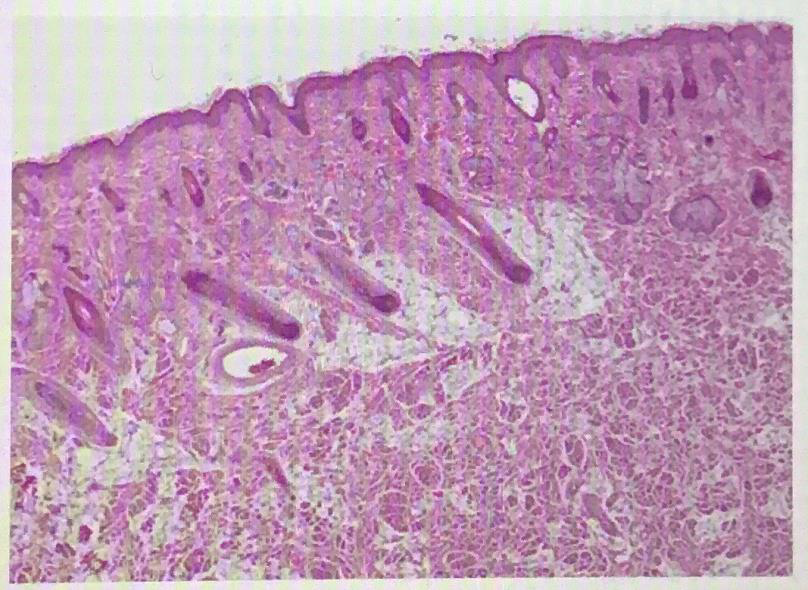

Oral mucosa

labial mucosa

vermilion zone

Dermal papillae

Hard palate rugae

Hard palate

Filiform papillae